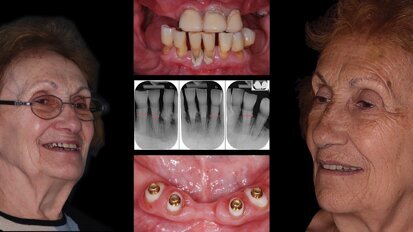

La formación es el futuro

El fundador y director del Centro Dental Multimédica de Guatemala describe la importancia fundamental que tiene la formación y la actualización en el ...